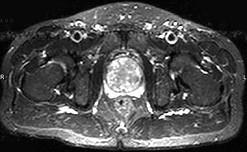

问题 男,60岁。尿频,淋漓不尽半年余。MRI扫描见前列腺明显增大并突入膀胱,最可能的诊断是 ( )

选项 A、膀胱乳头状瘤 B、未见异常 C、前列腺癌 D、膀胱癌 E、前列腺增生

答案 E